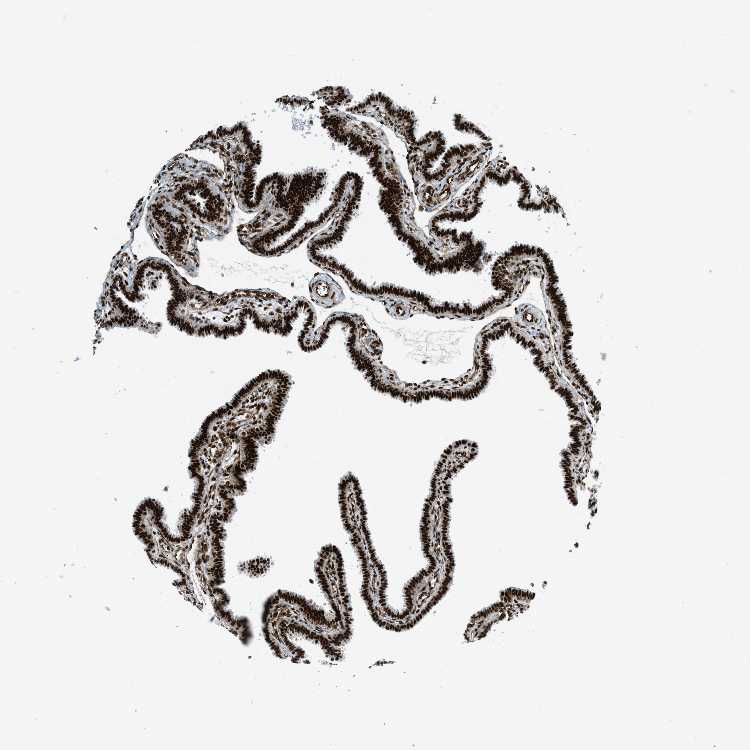

FALLOPIAN TUBE - Antibody stainingi

Antibody staining in the annotated cell types in the current human tissue is reported as not detected, low, medium, or high, based on conventional immunohistochemistry profiling in selected tissues. This score is based on the combination of the staining intensity and fraction of stained cells.

Each image is clickable and will lead to virtual microscopy that enables deeper exploration of all samples and also displays staining intensity scores, fraction scores and subcellular localization as well as patient and tissue information for each sample.

Antibody HPA016666

Glandular cells High